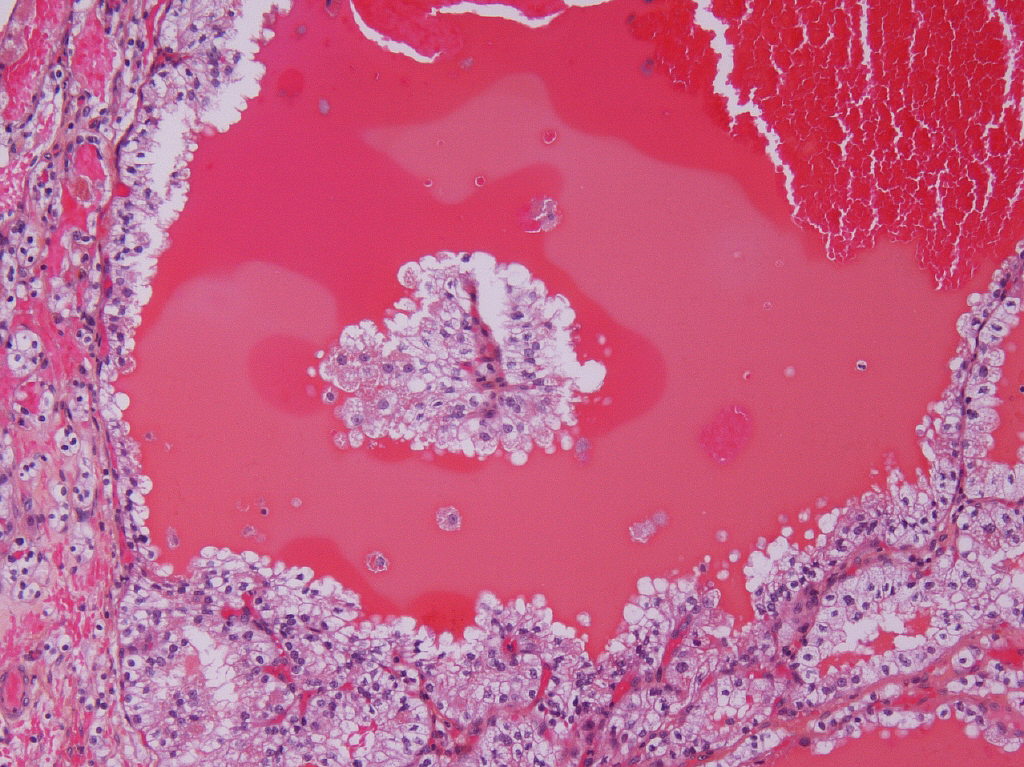

Classification of renal tumors